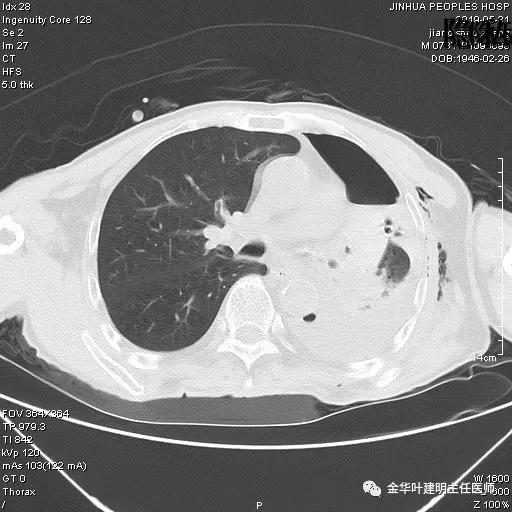

考虑左侧大量胸腔积液,遂进一步胸部CT检查:

以上是肺窗表现,下面为纵隔窗影像: